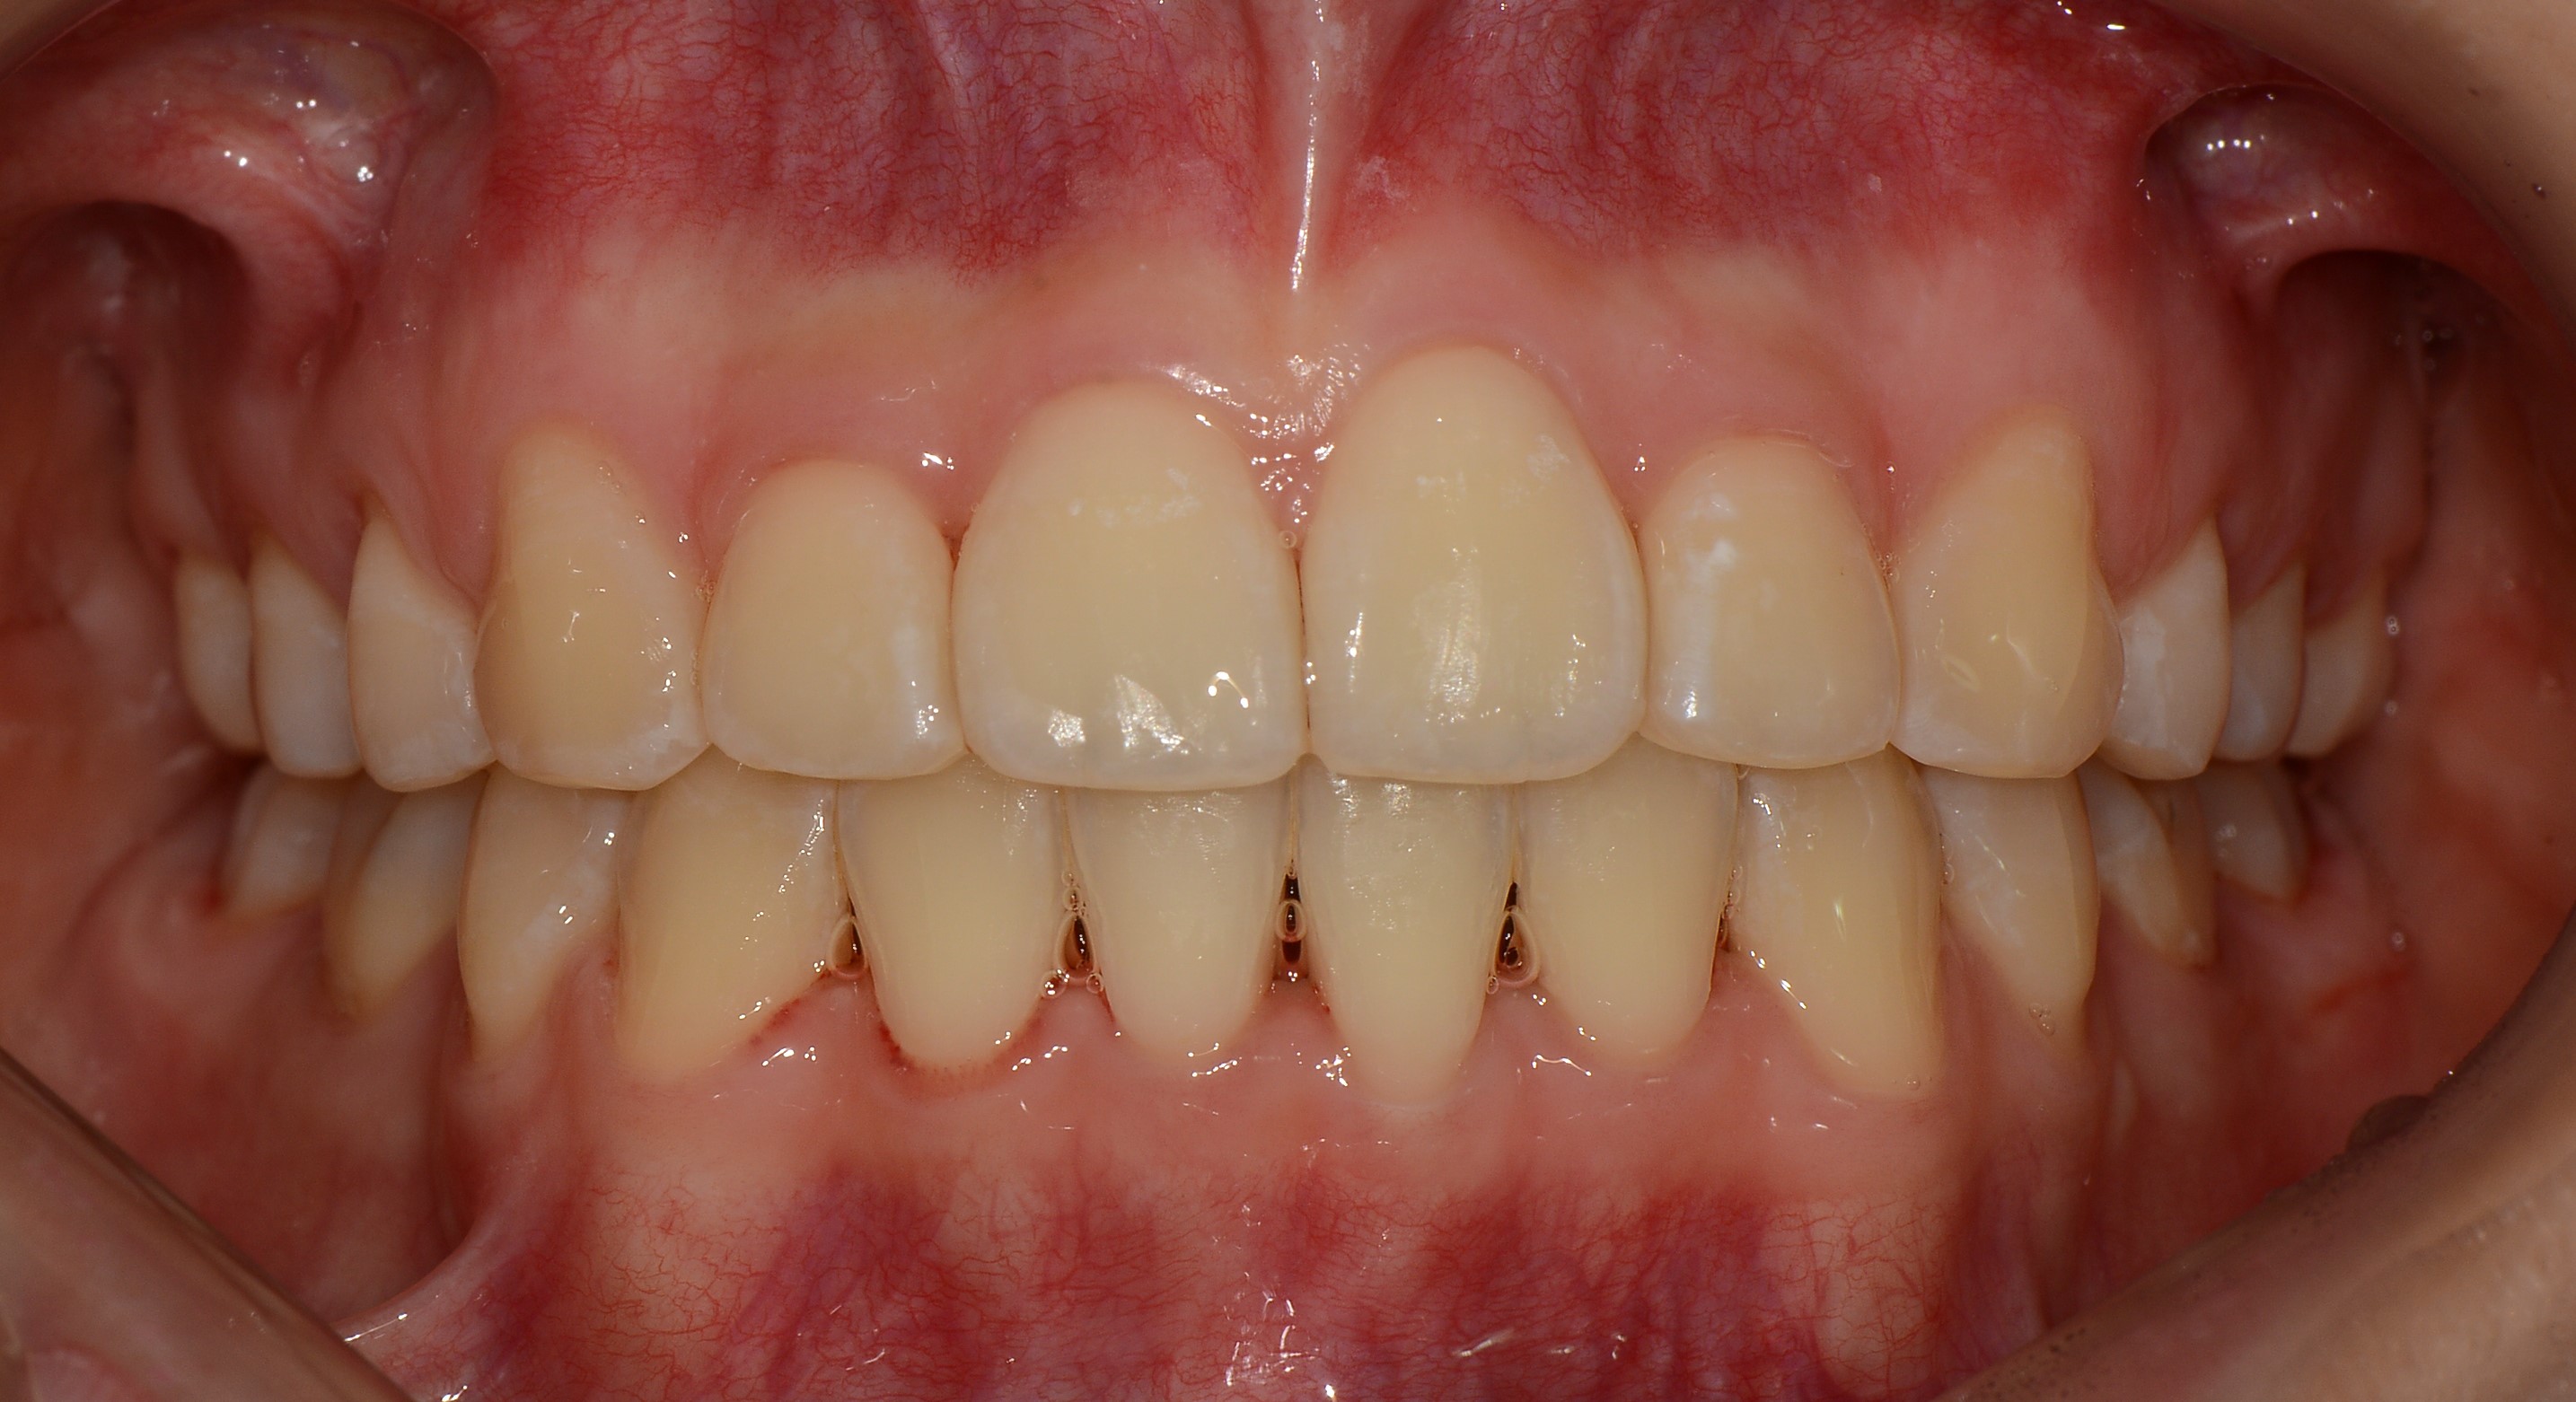

치료 후 사진입니다.